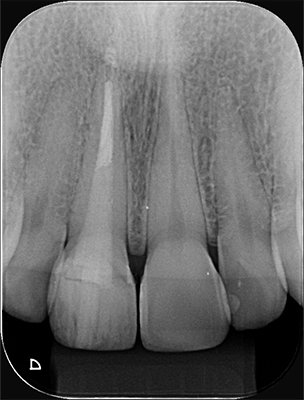

3 | Radiografia Inicial do dente 11 demonstrando adequado tratamento endodôntico e selamento com cimento de ionômero de vidro

28 | Radiografia final do dente 11.